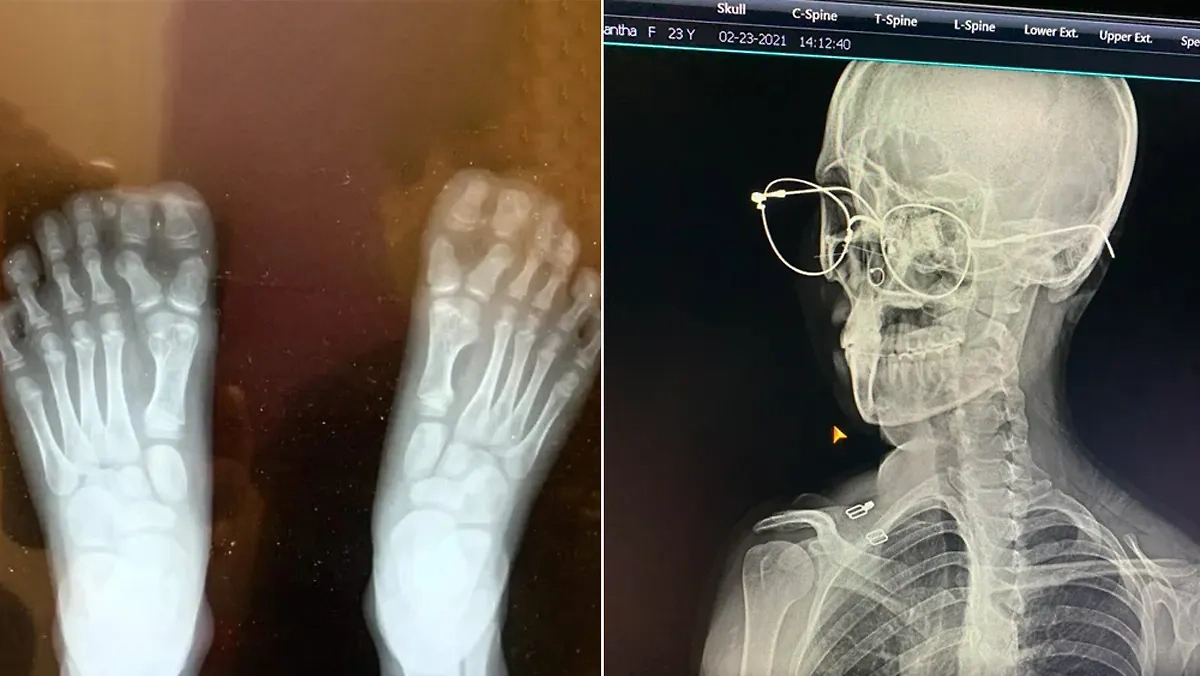

"Рентгенограмма стоп моего сына", — jsams18.

Фото © Reddit / jsams18

"Мне разрешили не снимать очки во время рентгена. Выглядит круто!" — Shahzoodo.

Фото © Reddit / Shahzoodoo

Reddit / jsams18, Shahzoodoo